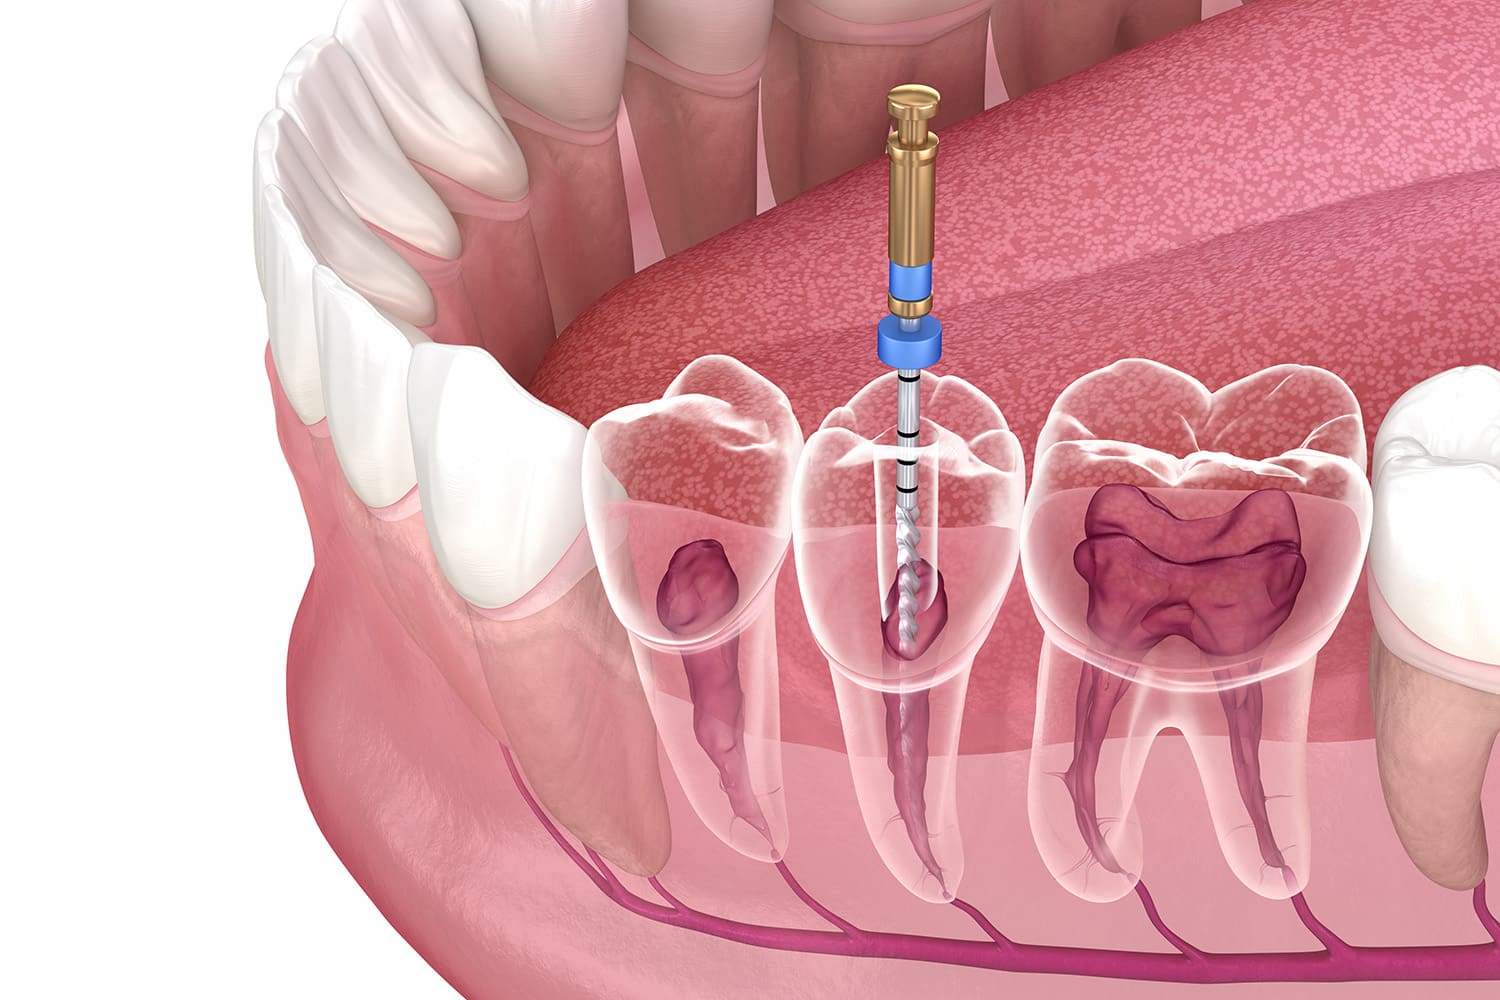

むし歯治療

むし歯は放置すると進行し、大切な歯を失うことにもつながりかねません。当院では、患者さんの不安に寄り添いながら、ご自身の目で状態を確認し、納得して治療を受けられるよう努めております。